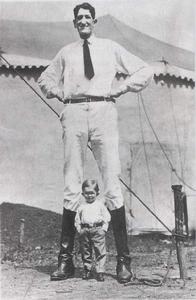

1、巨人症:生长发育过度,身高多在2m左右,生长过速可持续到20岁以上。食欲强,肌肉发达,性欲旺,在衰退期,精神不振,乏力,背佝偻,阳痿,迟钝。

(一)巨人症 单纯的巨人症较少见,成年后半数以上继发肢端肥大症,临床表现可分两期:

1.早期(形成期) 发病多在青少年期,可早至初生幼婴,本病特征为过度的生长发育,全身成比例地变得异常高大魁梧,远超过同年龄的身高与体重。躯干、内脏生长过速,发展至10岁左右已有成人高大,且可继续生长达30岁左右,身高可达210余cm,肌肉发达、臂力过人,性器官发育较早,性欲强烈,此期基础代谢率较高,血糖偏高,糖耐量减低,少数患者有垂体性糖尿病。